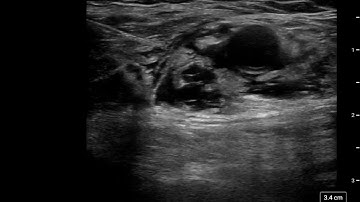

Axillary Brachial Plexus Block